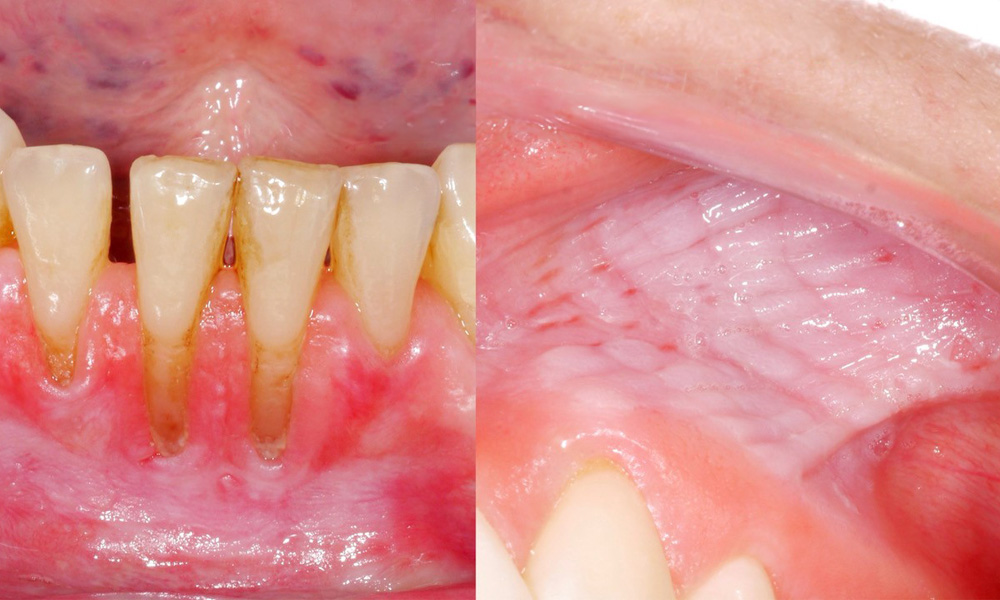

Es zeigte sich im Rahmen der klinischen Untersuchung, dass der regelmäßige Konsum von Snus folgende Auswirkungen auf die Mundschleimhaut haben kann:

• Ca. 80 % der Untersuchten, die täglich Snus konsumieren, wiesen Snus-induzierte Schleimhautläsionen auf.

• Jede zusätzliche Dose Snus, die pro Monat konsumiert wurde, stieg das Risiko für eine schwerere Schleimhautläsion signifikant an.

• Ca. 20 % der Untersuchten, die täglich Snus konsumieren, wiesen Snus-induzierte Gingivarezessionen auf.

• Für jedes weitere Jahr, in dem Snus bereits konsumiert wurde, stieg das Risiko für Snus-induzierte Gingivarezessionen signifikant an.